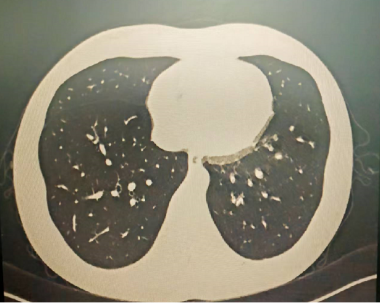

4月后再次复查胸部CT,提示病灶已经完全吸收。

明确诊断后我们给予了正规治疗,患者咳嗽症状迅速缓解,1月后复查胸部CT提示肺部病变大部分吸收。

以上是他的胸部CT影像,主要表现为左下肺炎症,片絮影+磨玻璃影。